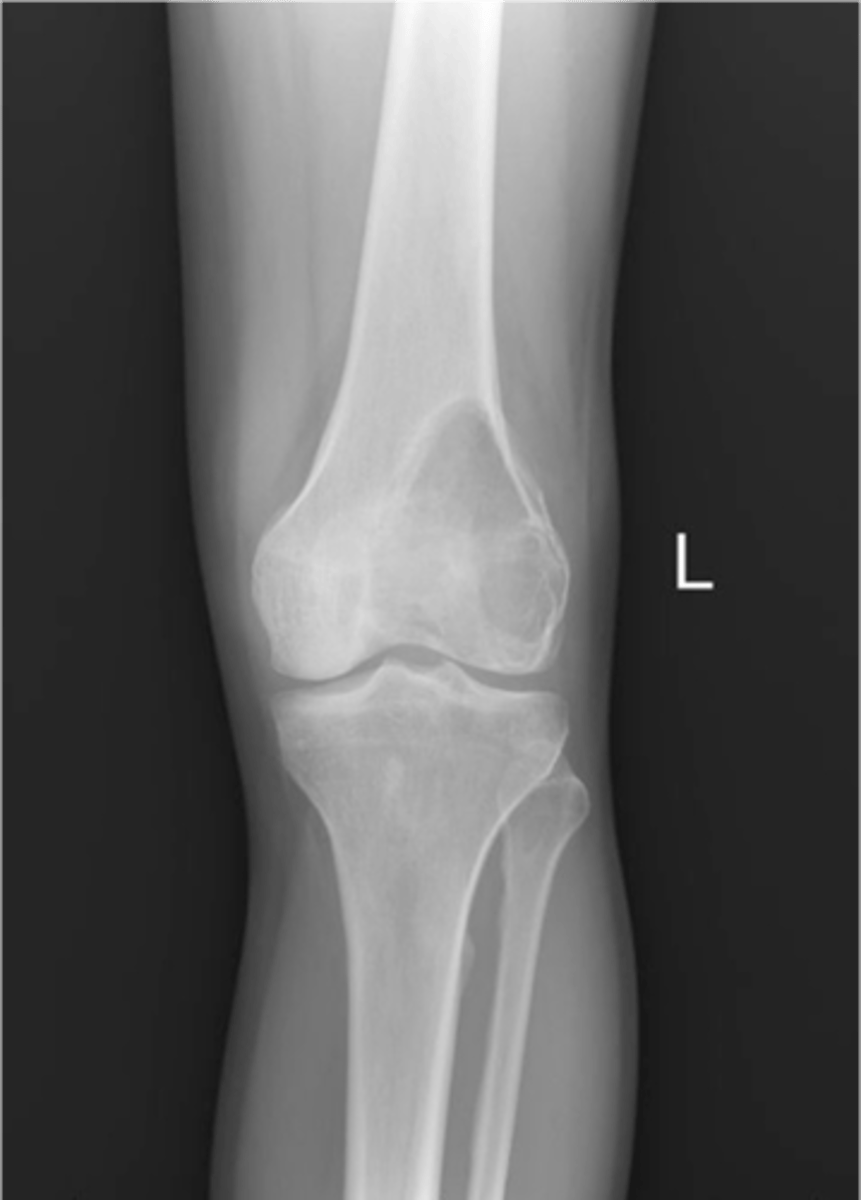

Non-ossifying fibroma

- Kids (<20 y.o.)

• Fibrous cortical defect (older term)

• Younger patient and smaller <2-3 cm

- M:F, 2:1

- Lower extremities

- Present in 30-40% of normal children

- Most asymptomatic (unless pathologic fracture)

<p>- Kids (&lt;20 y.o.)</p><p>• Fibrous cortical defect (older term)</p><p>• Younger patient and smaller &lt;2-3 cm</p><p>- M:F, 2:1</p><p>- Lower extremities</p><p>- Present in 30-40% of normal children</p><p>- Most asymptomatic (unless pathologic fracture)</p>

55

New cards

8 cm

Larger non-ossifying fibroma lesions >_____ may fracture

<p>Larger non-ossifying fibroma lesions &gt;_____ may fracture</p>

56

- Distal tibia

- Distal femur

- Proximal tibia

- Humerus

- Fibula

- Bones of the lower extremity (80-90%)

State the common locations for non-ossifying fibroma

<p>State the common locations for non-ossifying fibroma</p>

57

- Solitary

- Eccentric

- Geographic

- Multiloculated

- No malignant transformation

State the radiographic features of non-ossifying fibroma

<p>State the radiographic features of non-ossifying fibroma</p>

58

Geographic bone blister

ID radiographic feature of non-ossifying fibroma indicated by top arrow

<p>ID radiographic feature of non-ossifying fibroma indicated by top arrow</p>

59

Septations

ID radiographic feature of non-ossifying fibroma indicated by bottom arrow

<p>ID radiographic feature of non-ossifying fibroma indicated by bottom arrow</p>

60

Pathologic fracture

Non-ossifying fibroma with _____

<p>Non-ossifying fibroma with _____</p>